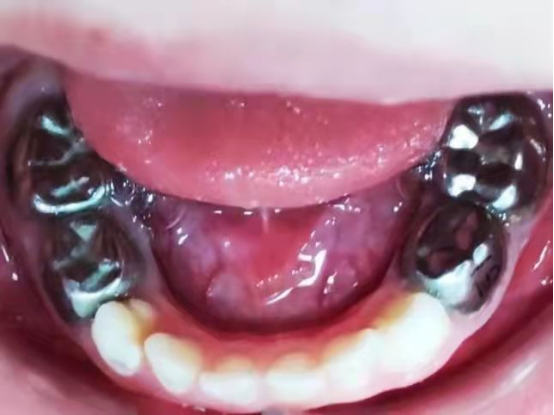

乳牙根管治疗是儿童口腔科常见的治疗方法,可是治疗结束后为什么医生都会为小朋友戴上这样一个金属小帽子,让小朋友们都变成了“钢铁侠”?

这个可爱的金属小帽子叫儿童乳牙金属预成冠,是一种预先成型的、与牙齿非常贴合的不锈钢金属牙冠。根管治疗完成后仍然存在继发龋、充填物脱落等可能性,这就需要有一个这样的金属小帽子套在乳牙上能够保护牙齿、增加牙齿的强度,确保乳牙正常地被恒牙替换。

对于乳磨牙的龋损,临床上通常采用玻璃离子或光固化树脂进行充填,但由于乳牙牙冠短、牙体硬组织薄、洞型制备深度有限、操作中隔湿困难等问题,其固位形及抗力形较差,充填物易脱落,最终导致治疗失败。并且由于常规充填术不能恢复乳牙解剖外形及高度,因此无法建立正常的咬合关系,不利于颌面部生长发育及诱导正常恒牙列的形成。金属预成冠的应用正好可以解决这些问题。

临床操作中预成冠的牙体预备去除组织较少,易恢复解剖外形、近远中径及其增加牙齿硬度、恢复牙齿外形和咀嚼功能;且操作比较简单,可有效解决玻璃离子、树脂类材料修复过程中所遇到的隔湿、继发龋及脱落等问题,减少了患儿后续就诊次数,延长牙齿存留时间直至其继承恒牙萌出。